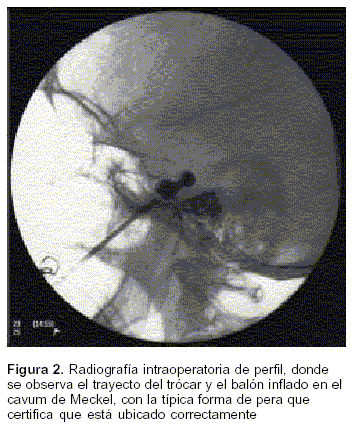

Compresion Percutanea Del Ganglio De Gasser Con Balon